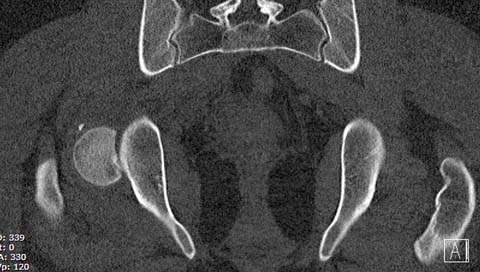

КТ после вправления - это последнее?

На мой взгляд, развитие артроза и AVN в большей степени зависит от давности вывиха и качества оперативной техники. Хирургический вывих бедра- не самая простая процедура и с подводными камнями, в остеосинтезе из переднего доступа тоже есть проблемы.

Здесь значимый задний край с подвывихом бедра кзади и острым краем вертлуги - задний доступ с вывихом и синтезом заднего края винтами и пластиной

Доступ выбирается на основании КТ, и ориентируются по расположению фрагментов. При расположении спереди - Smith Petersen или Watson Jones, а задние из Koher-Langenbeck. Все доступы имеют свои недостатки, повреждение медиальной артерии повышает риск, потому что больше чем 80% кровоснабжения головки за счет medial Circumflex!

Здесь клинические примеры: Первый случай передний доступ, второй с ICP monitor Flipp Trochanteris

и с переломом заднего края.